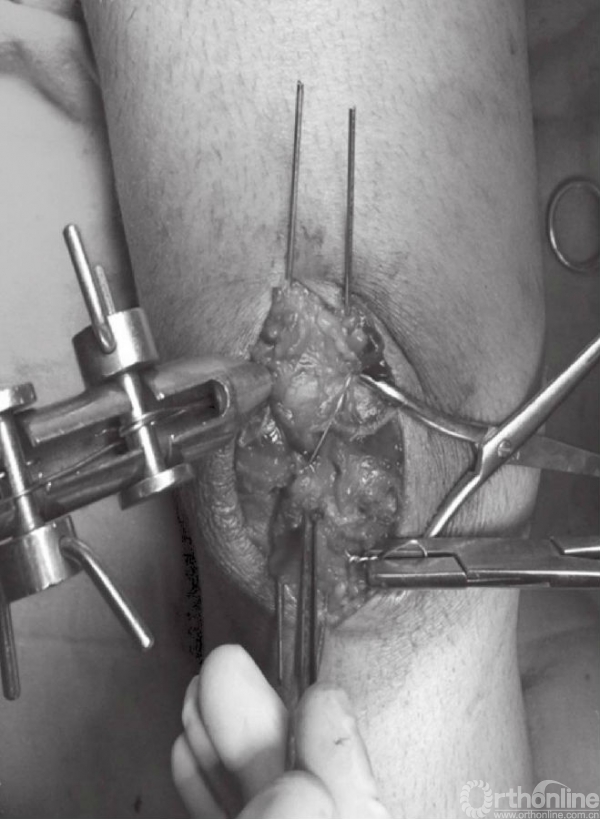

应仔细探查关节,以辨识游离骨块以及关节面损伤(图6)。此时,可对骨折进行复位,并以复位钳进行临时固定。检查骨折复位情况以及关节稳定性,关节内骨块的解剖复位是非常重要的。术中复位困难,可能是因为小骨块或者软组织嵌于骨折端。

图6 应仔细探查关节以辨识游离骨块以及关节面损伤